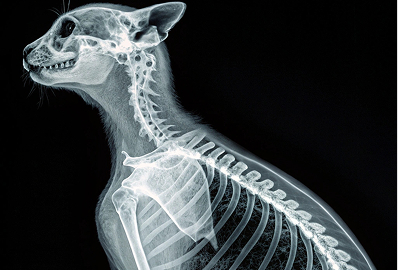

Рентген для животных

Какой рентген делают животным?

Рентгенологическое исследование затрагивает такие органы у собак и кошек:

• Легкие, бронхи. Рентгенография грудной клетки используется для диагностики различных заболеваний дыхательной системы: пневмония, бронхит, обструкция дыхательных путей.

• Сердце и сосуды. Рентгеновские снимки используются для оценки размеров, формы сердца, а также для выявления увеличенных размеров, массы сердца, других патологий.

• Желудочно-кишечный тракт. Рентгенография используется для выявления инородных тел, опухолей, заболеваний ЖКТ, а также для оценки проходимости, функционирования этих органов.

• Печень, селезенка. Рентгенография брюшной полости проводится для оценки размеров, формы и структуры органов гепатобилиарной системы, а также для выявления опухолей, других патологий.

• Мочеполовая система. Рентгенография помогает в оценке состояния почек, мочевого пузыря, выявлении камней, обструкций, других заболеваний.

• Кости, суставы. Рентгеновские снимки необходимы для лечения переломов, изучения деформаций, дисплазии суставов, других ортопедических проблем.

Это лишь несколько примеров органов, структур, которые могут быть изучены при рентгенологическом исследовании.

Что можно увидеть на рентгене?

Рентгенография является основным методом диагностики переломов костей, деформаций, дисплазии суставов, артрита, других заболеваний опорно-двигательной системы. Рентгеновские снимки грудной полости показывают наличие пневмонии, бронхита, опухолей, инородных тел, других аномалий в легких и дыхательной системе.

Рентгенография позволяет оценить размеры, форму сердца, выявить увеличение сердца (кардиомегалия), определить состояние сосудов, выявить аномалии кровообращения. На рентгеновских снимках можно обнаружить инородные тела, опухоли, заболевания желудочно-кишечного тракта, обструкции, другие аномалии.

Рентгенография помогает оценить размеры, форму, структуру печени, селезенки, почек, мочевого пузыря, выявить камни, опухоли, другие патологии. На рентгеновских снимках видны различные мягкие ткани, такие как мышцы, жировая ткань и органы в грудной и брюшной полостях.